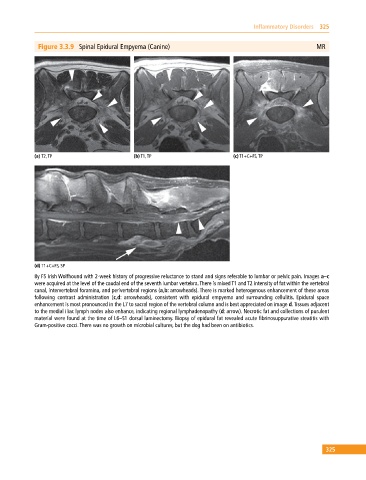

Figure 3.3.9 Spinal Epidural Empyema (Canine) MR

(a) T2, TP (b) T1, TP (c) T1+C+FS, TP

(d) T1+C+FS, SP

8y FS Irish Wolfhound with 2‐week history of progressive reluctance to stand and signs referable to lumbar or pelvic pain. Images a–c

were acquired at the level of the caudal end of the seventh lumbar vertebra. There is mixed T1 and T2 intensity of fat within the vertebral

canal, intervertebral foramina, and perivertebral regions (a,b: arrowheads). There is marked heterogenous enhancement of these areas

following contrast administration (c,d: arrowheads), consistent with epidural empyema and surrounding cellulitis. Epidural space

enhancement is most pronounced in the L7 to sacral region of the vertebral column and is best appreciated on image d. Tissues adjacent

to the medial iliac lymph nodes also enhance, indicating regional lymphadenopathy (d: arrow). Necrotic fat and collections of purulent

material were found at the time of L6–S1 dorsal laminectomy. Biopsy of epidural fat revealed acute fibrinosuppurative steatitis with

Gram‐positive cocci. There was no growth on microbial cultures, but the dog had been on antibiotics.